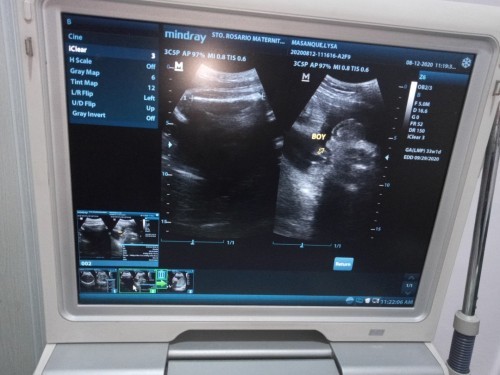

33weeks pregnant Mga mommy 33 weeks na kme ni baby Edd ko is September 29.Sabi ng OB ko 3kg na si baby.Pinag da diet na niya ako.Normal lang po ba ang 3kg? Going to 8mos palang ako at nxt month pa edd ko. Salamat

Pang full term weight na po yun mamsh. I am also 33 weeks pregnant edd sept 30..my baby's estimated fetal weight as of last UTZ nung 31weeks ako was only 1.8kgs and pinapa diet na ako ni OB.

same tau ng edd 33weeks and 3days na ako today.😊 kaso timbng ng baby ko nong last utz ko which is 30weeks ako non 1226 pa lng siya maliit kasi tyan ko

same po tau September 29 2.1kg. Pa lng c baby ngaun.. less carbs kna mamsh more on vegetables ka nlang and fruits yan gnagawa q. 😊

same tayo 33weeks but Sept 27 edd ko. Sa sept 7 pa titimbangin at susukatin baby boy ko😊